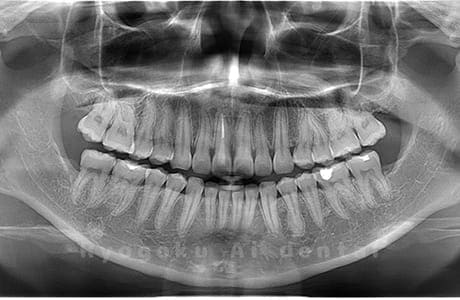

水平埋伏の親知らず

歯茎の中で完全に横に生えてしまうタイプです。

この親知らずを水平埋伏智歯と言います。このタイプはほとんどが下顎のケースです。真横に生えているので抜歯の際は難易度が高く2~3つに砕いて分けて抜歯をします。